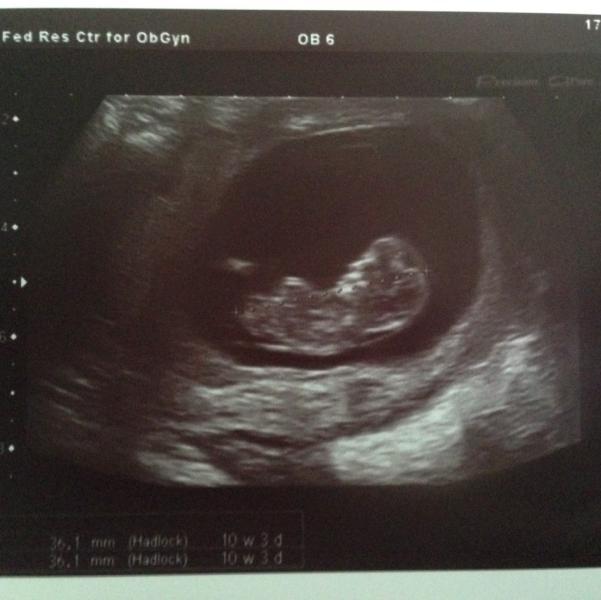

Растет человек😊😊 Каждый день на него смотрела бы! Дали направление в третий роддом на первый скрининг, может кто-нибудь его там проходил? Большие очереди? Можно записаться на какое-то время заранее?